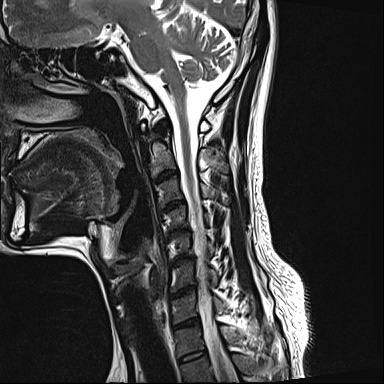

Ű 177 64 40 ()ijħ ڸǥغ ǥغ ϱ ȣϴ 1C.ٸǷ 6C.ڸ 6C.ھ Ḳ 6C.ڻ ()ũ( ߰Ż) ڸ(߹) ĿCڸ(ĸ) Ը ũ(߰Ż)ġ, , Ḳ ġ Ǵ ġ ()ijħ ڸǥغ ǥغ ϰ ߴ ġ 2008~2011 ð ɾƼ ǻ ۾ Ҷ, Ʈ , ȸ ϰ, . 2011 4 : 6,7 ߰Ż , ڸ ó ļ ַ ġ . ü, ߳, ѹ, ũ, ֻġ ġ غ ȿ ġ ġᰡ Ұ Ǵϰ ֿ 3ȸ ƮĪ ణ ȣ. 2014 5 20 濡 ħ ڱ ϰ · ư. (ֱ ϰ, Ʈ ϰ ) а ũ ִ ֺ, Ʒ κп δֻ 1ȸ ̰, ణ . ûϸ鼭 ȸԲ ϴ ûϰ ߽ϴ. Ϻϰ ȸ ּ. mriԴϴ. |

| Ȩ | [ֹȣ : 20140527121055zoosa***] ϸ 2 ð ȸ ȣ ڷ ø ȭ帱 Դϴ. mri Դϴ. ġẸٵ ߿ ȭŰ ʴ ̰ ȸų ˾ƾ ϰ ߵʰ ؾ մϴ. ȸǴ ȸǴ 30 ü ȸǴ ƮĪ ȸԲ ȭ ˷帱 Դϴ. ȭ ˷帮 ̴ ϱ ȭ Ÿ پų Ȳ ãư鼭 ̱ Ȯ ۵ ֽϴ. ū Ͻð غñ ٶϴ. Ϻ ȸ ȸ ñ ٶϴ. | 05/28 [14:40] | ||

-----ù Դϴ.------- 2011 mri˻ 2008 ó Ͱ ö Ȱ ϰ ߵٰ ̷ ġ ߾ ϰ ߴµ ٷַ Ʈ 帮Ʈ Ͽ 3 ϴ ȭ Ǿ ġ ʴ. Ȱ Ƽ ⺻ ƮĪ Ͽ ߾ dz ϰ ۳ ְ 3 80 ִ . 1300~1400 ġḦ ϰڴٰ Ƽ鼭 Դϴ. δ 10ȸ Ϸ ѹϴµ 12 ϰ ϰ δġ ڷ ̷ | 05/28 [21:29] | |||